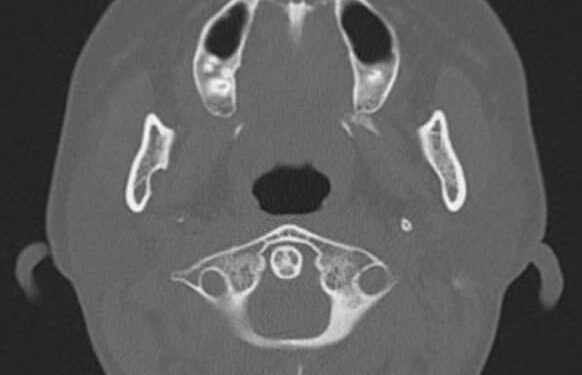

Sau khi kiểm tra, các bác sĩ sẽ đề nghị chụp X-quang Panorex (chụp X-quang miệng và hàm), chụp CT scan để khảo sát chính xác

Gần đây, Khoa Răng Hàm Mặt có tiếp nhận bệnh nhân L.T.X. (nữ, 33 tuổi), đã điều trị tủy vào bọc răng sứ các răng 11, 21 cách đây 3 năm. Bệnh nhân đến khám vì bị sưng nề môi trên và chảy dịch mủ vùng răng cửa hàm trên. Sau khi chụp phim và thăm khám, bác sĩ phát hiện nang xương hàm trên khá to, kéo dài hết 4 răng cửa hàm trên. Nguyên nhân do răng 11 điều trị tủy không tốt dẫn đến hình thành nang xương, gây tiêu xương, nang không đau, to dần, gây biến dạng mặt và cần phẫu thuật để loại bỏ nang xương.

Ngay sau khi tiếp nhận, bệnh nhân đã được điều trị tủy các răng 12, 21, 22, điều trị tủy lại R11. Sau đó, tiến hành phẫu thuật để nạo khoét toàn bộ nang và cắt chóp các R11, 21, 12, 22.